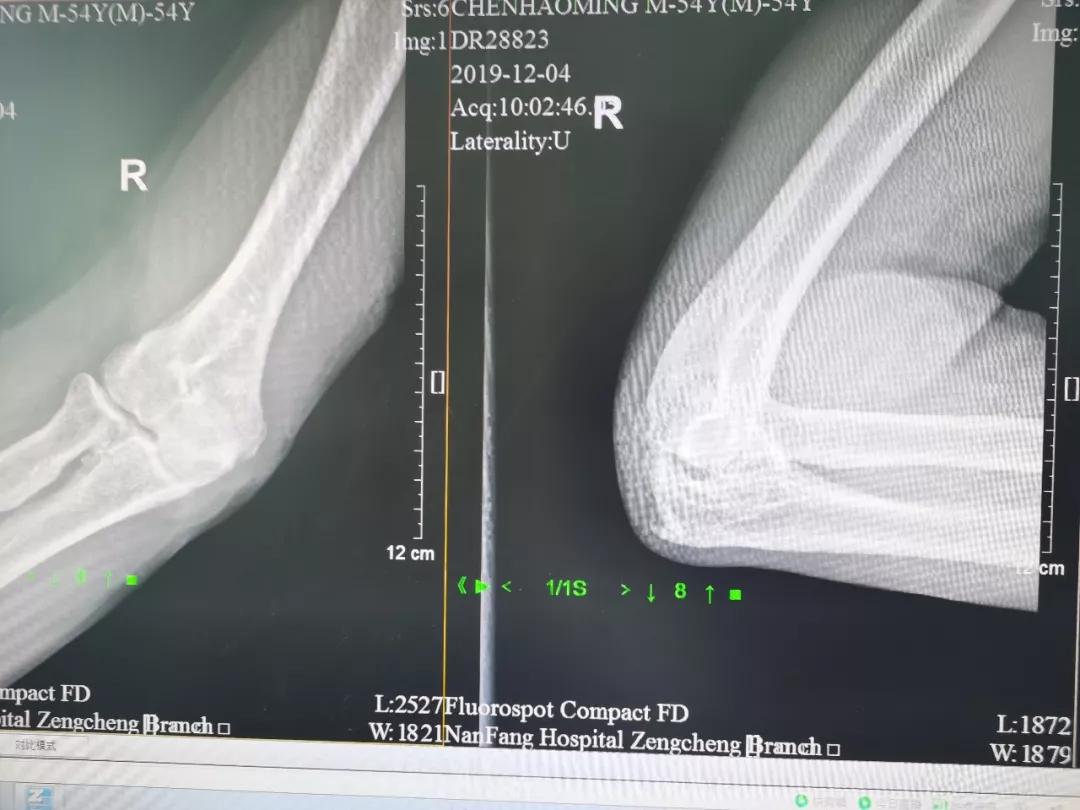

萝卜教授和同科室的莫捷华副主任医师根据陈叔肩部、肘部的X光片一起分析陈叔的病情,确诊是右肩袖损伤、右肘关节僵硬,经过讨论,一致决定给陈叔的肩、肘同时行两个部位的关节镜微创手术。

术前影像资料